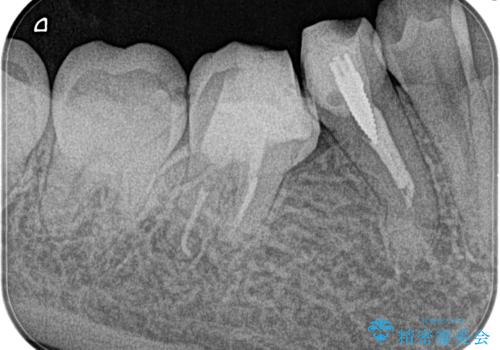

【湾曲根管】奥歯がズキズキ痛い

担当医 河口智英